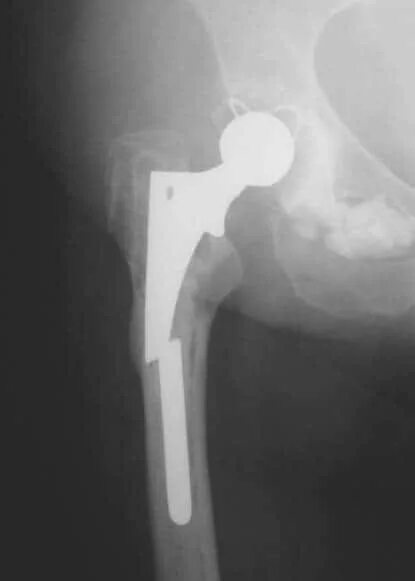

Срок службы тазобедренного эндопротеза